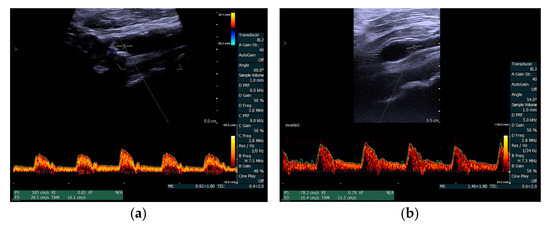

2. Materials and Methods

3. Results